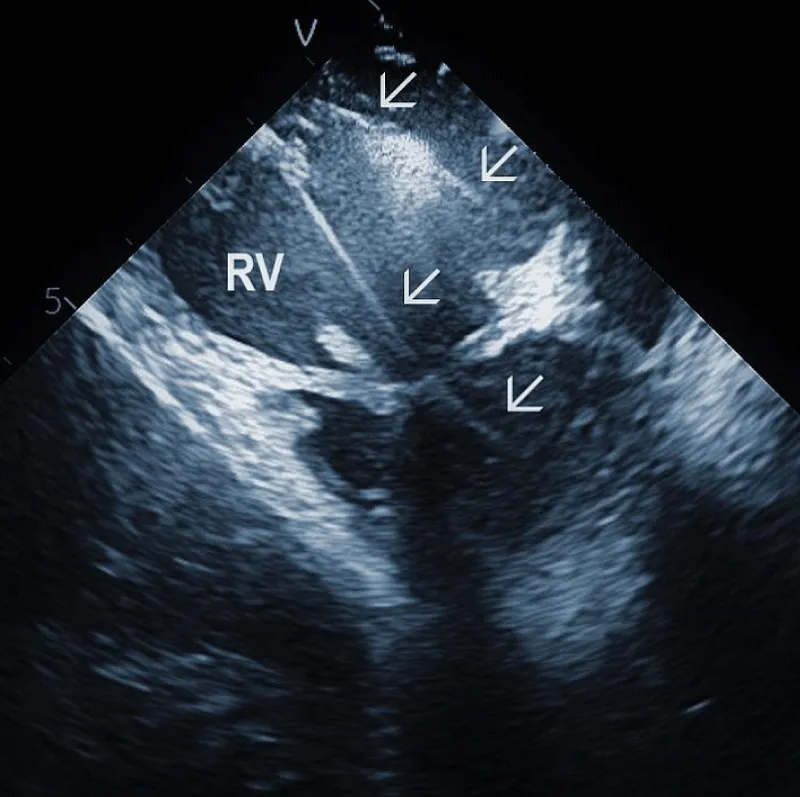

Areas of fibrous adherence: Areas of fibrous adherences or attachments (i.e., scar tissue) can be visualized as echo-dense structures along the lead course (Figure 3A). Multiple leads are usually attached by fibrous tissue together (Figure 3B). The location of fibrous adherence can be anywhere in the course of the lead [7,10]. In a study by Bongiorni, et al. [7], scar tissue was noted by ICE in the subclavian vein, innominate vein, and the right ventricle in about 80%, 68%, and 68% of cases, respectively. Sadek, et al. [10] described attachments less frequently – only in 18/50 pts (36%), predominantly intracardiac. Anecdotal cases were reported on specific locations of adhesions, such as a vulnerable “stalk” attaching the papillary muscle to the RV endocardium [18]. Notably, the fibrous attachment presence correlated with the extraction procedure’s difficulty. These patients were more likely to have a “complex” extraction procedure. Subjects who did not have evidence of lead attachment were less likely to require the advancement of the extraction sheaths past the superior vena cava and less likely to require advanced extraction tools such as snares.

Figure 3A: Fibrous adherences (arrow) attaching the lead within the superior vena cava (SVC). AO: Ascending aorta.

Figure 3B: A convolute of 2 leads attached together with fibrous tissue at the level of tricuspid valve (arrows). RA: Right Atrium; RV: Right Ventricle.